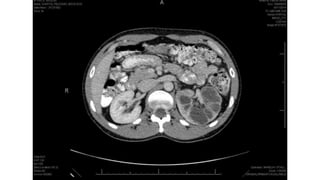

 Intestinal

 Hepatoesplênica

Renal